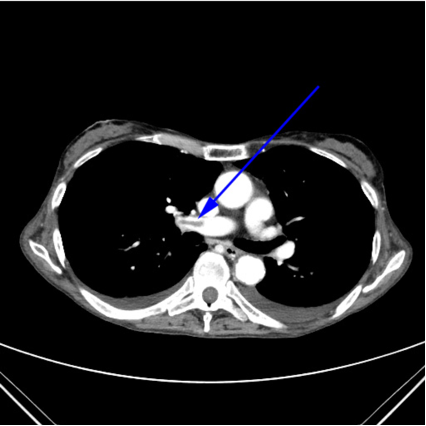

Lungeemboli:

- Embolier (mørke) omsluttet af blod (lyst)

Diagnose?

A

Lungeemboli